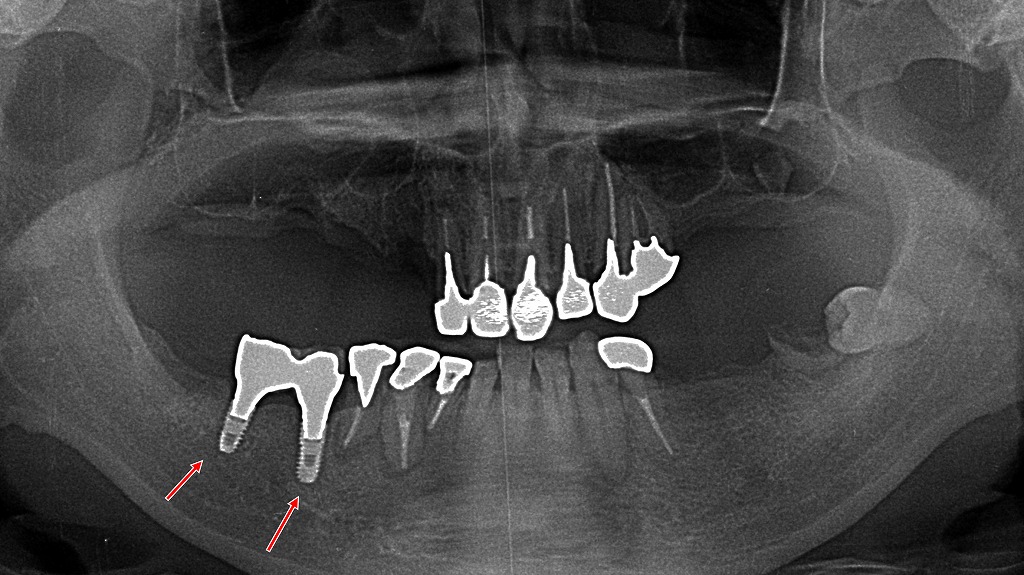

- 5.3. 🔩金属床義歯の装着例

🔩金属床義歯の装着例

金属床義歯の装着前の正面観

上顎に金属床義歯を装着します。前歯にクラスプがかかると目立つので、上顎左2番3番はコーヌステレスコープ義歯の内冠がセットされています。

金属床義歯の装着後の咬合面観

上顎口蓋を覆うように金属床が作られています。奥であまり目立たないので、小臼歯2ヶ所にはクラスプを設置しています。